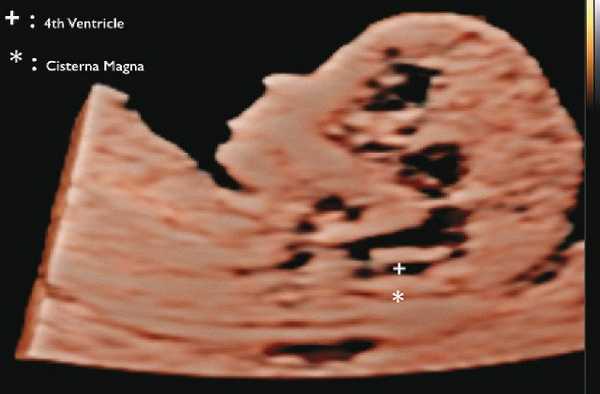

Расщепление позвоночника (spina bifida)

В прошлом лечащие врачи и врачи ультразвуковой диагностики проводили ультразвуковой скрининг для выявления дефектов нервной трубки, главным образом открытого расщепления позвоночника (spina bifida), во II триместре. В последние годы предложены ранние ультразвуковые маркеры на 11-14-й неделе беременности (внутричерепное пространство, использование БПР и соотношения БПР/ПРЖ (поперечный размер живота)), которые позволяют выявить у некоторых плодов высокий риск открытого расщепления позвоночника (рис. 7) 11.

Рис. 7. Внутричерепное пространство при ультразвуковом скрининге по поводу открытого расщепления позвоночника.